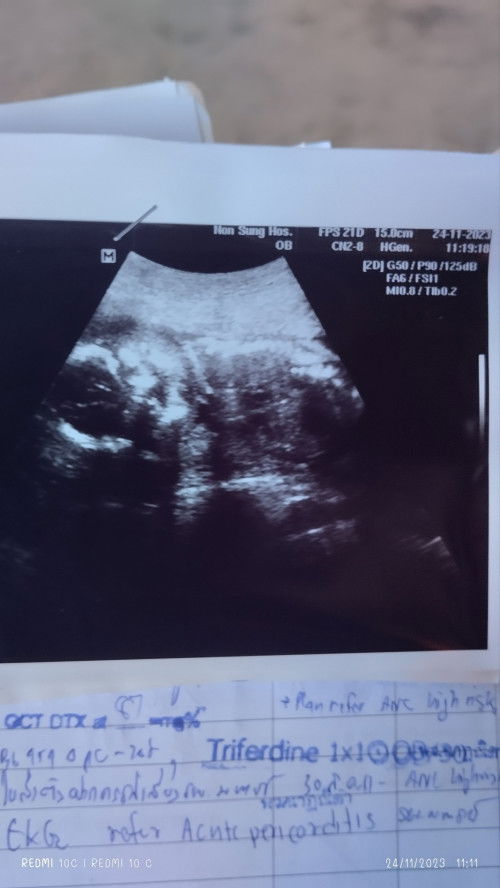

หมอบอกน้องเป็นผู้หญิงคะ แต่แม่ดูไม่ออกเลย